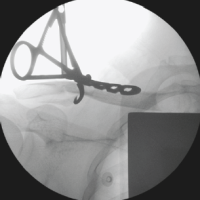

They meticulously removed the adhesions while protecting the underlying vital structures (Vid). A 6–-8 cm straight incision was made over the fracture site, which was opened in layers to access the fracture. After cleaning the fracture ends, we encountered difficulty in reducing the fracture due to the inability to use forceps or retractors. Consequently, we opted to place a 3.5 mm Schanz screw in the proximal fragment and applied traction with a periosteal elevator to facilitate reduction under thoracoscopic guidance (Fig. 4).

Figure 4: Reduction of fracture by Schanz screw and periosteal elevator.

The reduction was stabilized with K-wires. We then decided to use two low-profile 3.5 mm titanium locking plates in a railroad technique, pre-bending them to match the contour of the sternum (Fig. 5).